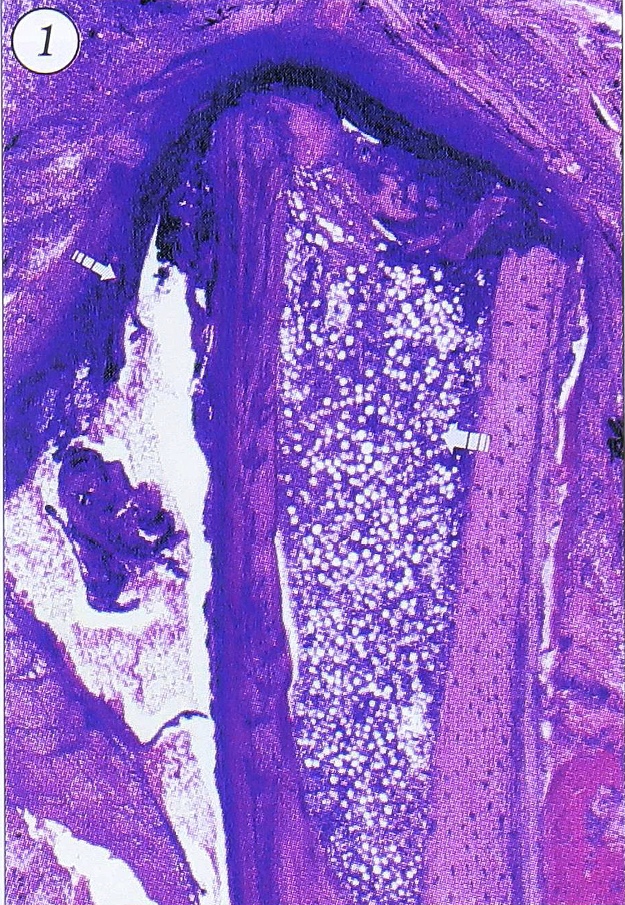

Строение очагов остеомиелита в острой и хронической стадии. В острой стадии ТО после остеотомии с инфицированием у крыс поражение не носит характера четко очерченного очага, так как еще не завершено формирование капсулы. В центре располагается обширная зона некроза костного мозга, по краю которой наблюдается картина серозно-гнойного воспаления (рис. 1, 2), а к 7-м суткам краевые отделы некротизированного участка костного мозга находятся в состоянии гнойного расплавления. Через 2-3 сут после начала острого инфекционного воспаления, кроме альтеративно-экссудативных и деструктивных изменений, в реактивной зоне начинается пролиферация незрелых клеток: фибробластов, остеобластов, эндотелиоцитов, миобластов (в пароссальных мягких тканях) и др. Ширина этой зоны в сроки 3—7 сут увеличивается. Через неделю после травмы идет активный рост грануляционной ткани, которая может длительно сохраняться в очаге в виде внутренней оболочки капсулы остеомиелитического очага, в то время как внешние отделы грануляционной ткани, созревая, образуют фиброзную оболочку.

Рис. 1. Острый травматический остеомиелит большеберцовой кости крысы, сочетающийся с травматическим инфарктом кортикальной части кости и костного мозга (толстая стрелка); в перифокальных мягких тканях — гнойное воспаление (тонкая стрелка). Срок 3 сут. Ув. 25. Здесь и на остальных рисунках окраска гематоксилином и эозином.